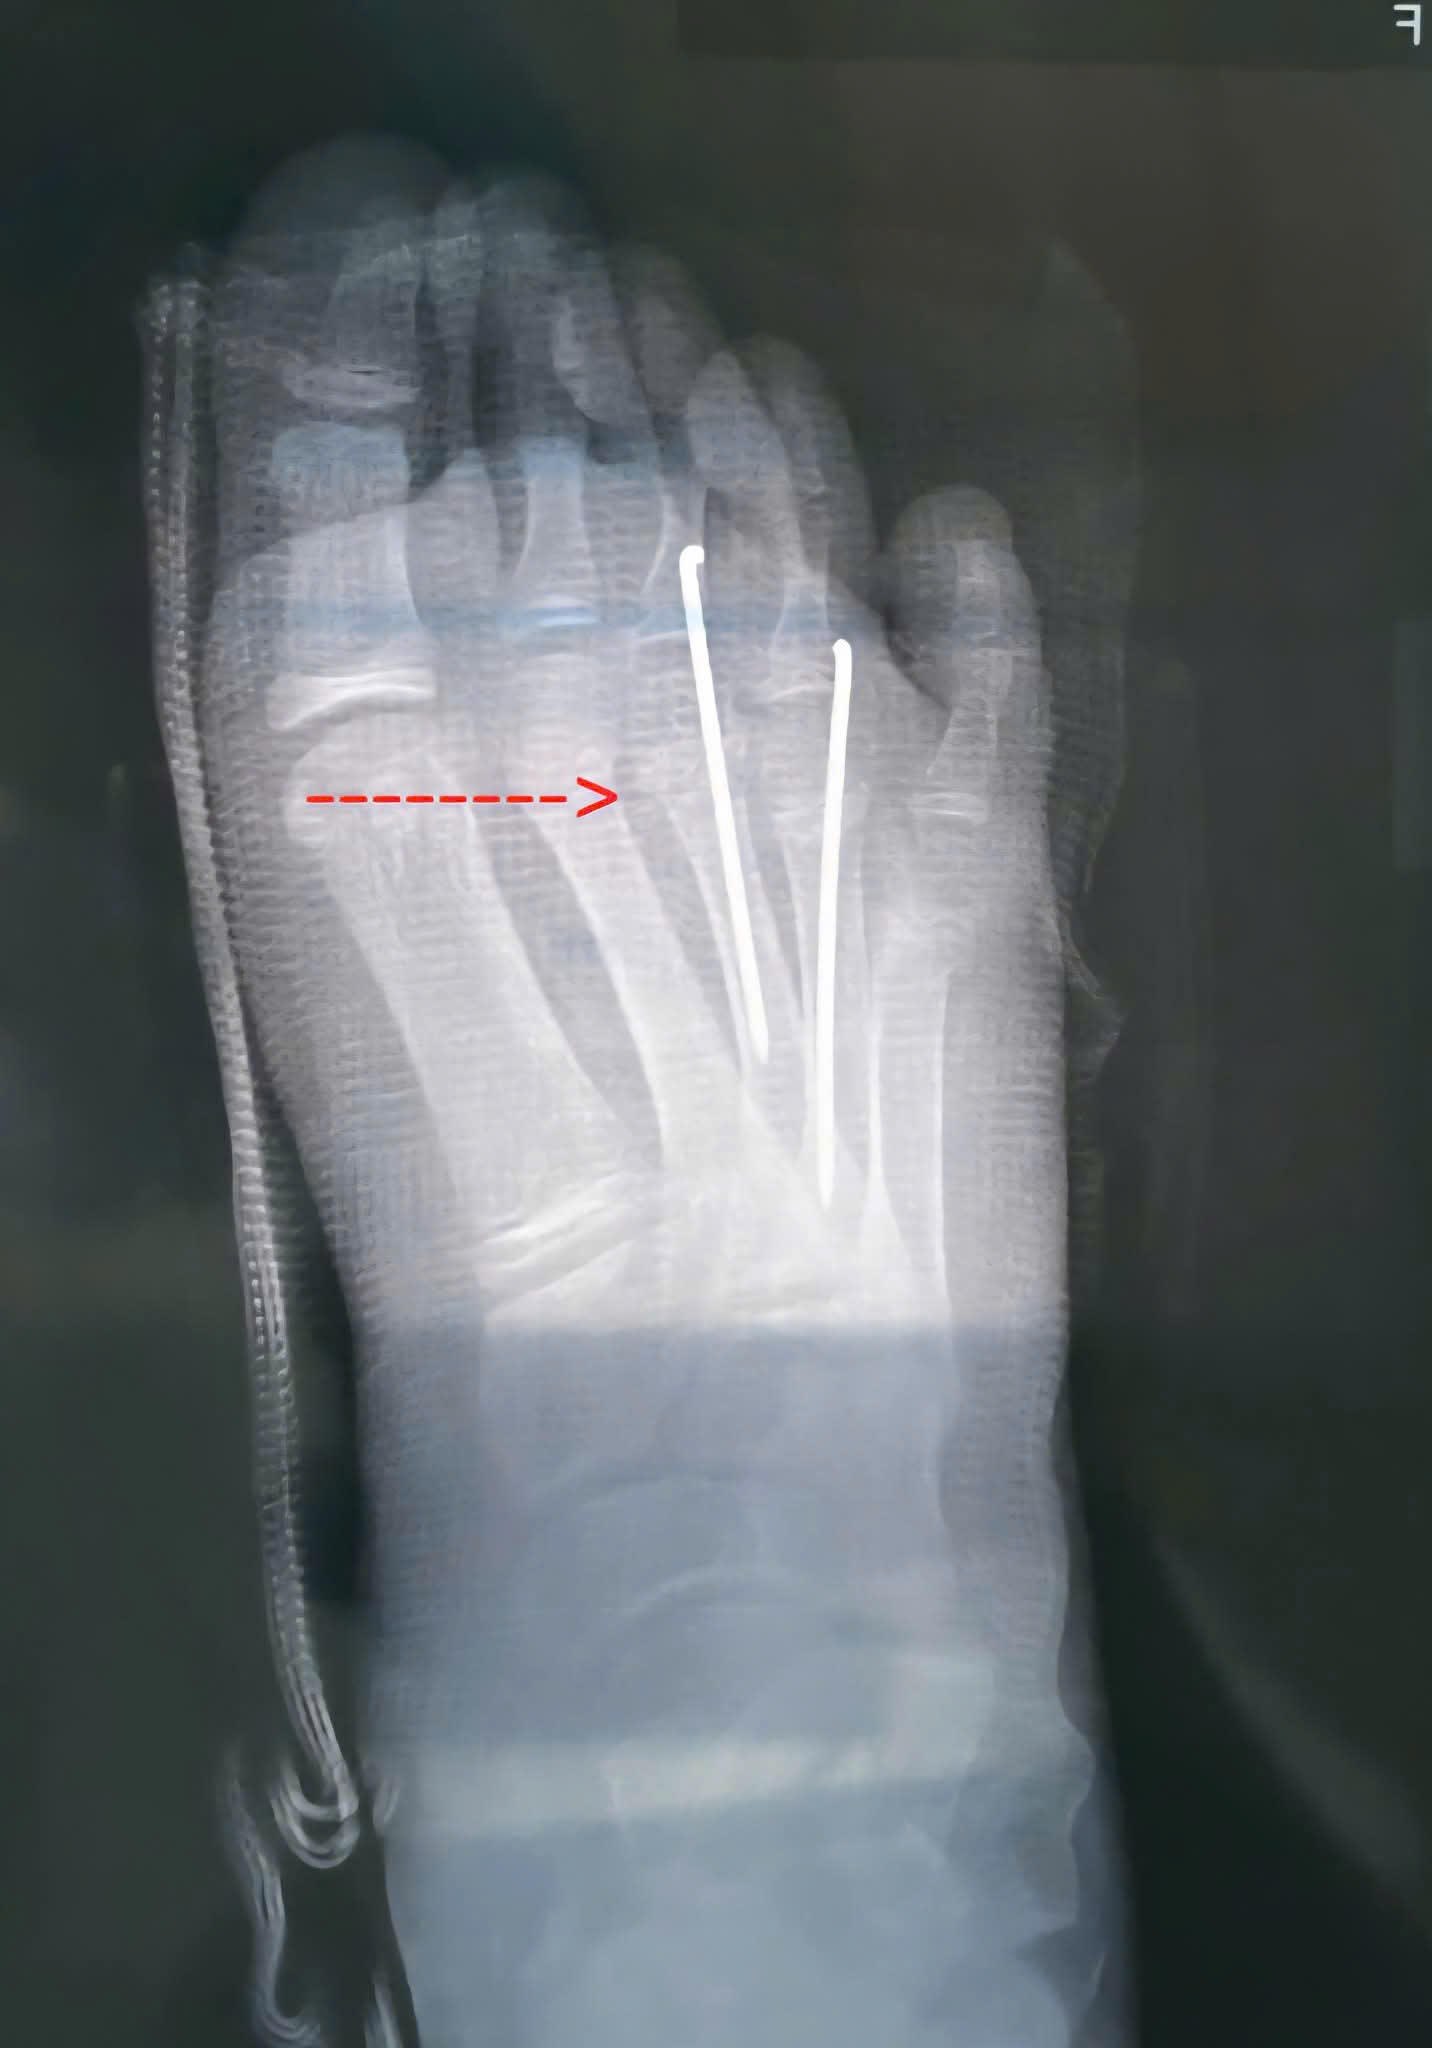

❤️ Bệnh nhân nữ, 8 tuổi không may bị trượt chân té ngã gãy kín xương bàn 2 đến 5 bàn chân trái. Bé được 1 phòng khám lớn cho bó bột và dặn 4 tuần bỏ bột không hẹn tái khám. Bệnh nhân về thấy còn đau, sưng người nhà đưa đến Trung tâm y tế Thành phố Thuận An được các Bác sĩ chuyên khoa Chấn thương chỉnh hình khám, x quang kiểm tra thấy xương bàn 3 và 4 còn di lệch nhiều cần phải phẫu thuật nắn chỉnh lại. Từ khi Bệnh nhân bị tai nạn đến khi mổ là gần 10 ngày xương gãy đã có nhiều cal xương nên các Bác sĩ phải phá cal và kết hợp xương xuyên kim Kirschner để cố định xương gãy. Kết quả sau mổ xương gãy đã được nắn chỉnh hết di lệch, giúp xương lành tốt và không ảnh hưởng đến chức năng sau này của bàn chân.